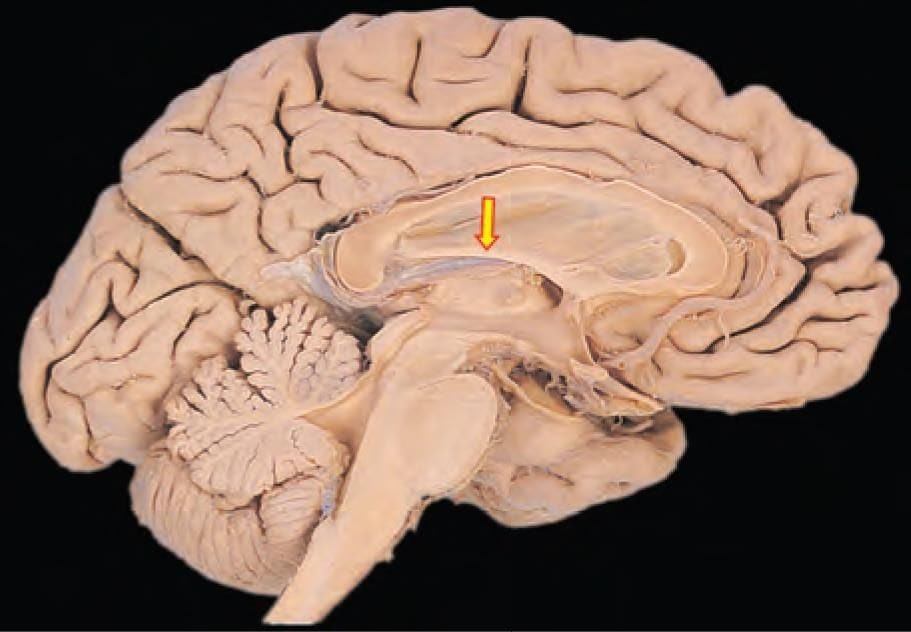

Mention the arterial supply of the marked structure: (INI-CET May 2022)

Detailed Solution for Test: Anatomy - 3 - Question 2

The arrow mark indicates the rostrum section of the corpus callosum, which is supplied by the anterior cerebral artery and the anterior communicating artery. The blood supply to the corpus callosum comes from:

• A branch of the anterior communicating artery (the median callosal or subcallosal artery)

• The pericallosal artery (the distal portion of the anterior cerebral artery)

• The posterior pericallosal artery (typically a branch of the posterior cerebral artery)

Additional notes:

• The splenium of the corpus callosum is supplied by the posterior pericallosal artery (a branch of the posterior cerebral artery).

• The middle cerebral artery supplies the lateral aspect of the corpus callosum.

It is important to note that the rostrum of the corpus callosum (commissural fibres) connects the orbito-frontal cortex of both sides for inter-hemispheric transfer of information.